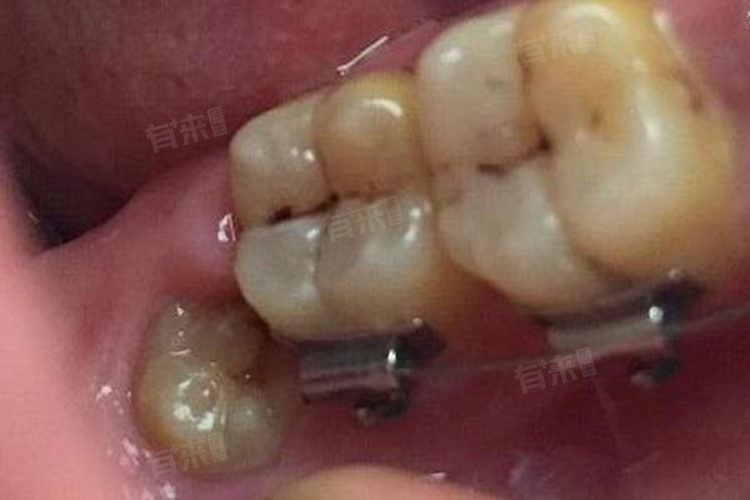

- 智齿拔除的时间还与智齿的生长位置、牙根形态等多种因素有关。正位智齿,即智齿完全萌出且位置正常的,拔牙过程相对简单,所需时间较短,通常10-20分钟就能完成。而阻生智齿,如水平阻生、近中阻生等,拔牙难度增大,所需时间也会相应延长,可能需要30分钟至1小时甚至更长时间。对于牙根形态简单、为单根且较直的智齿,拔牙相对容易;而对于牙根分叉多或弯曲的智齿,拔牙难度则会增加。